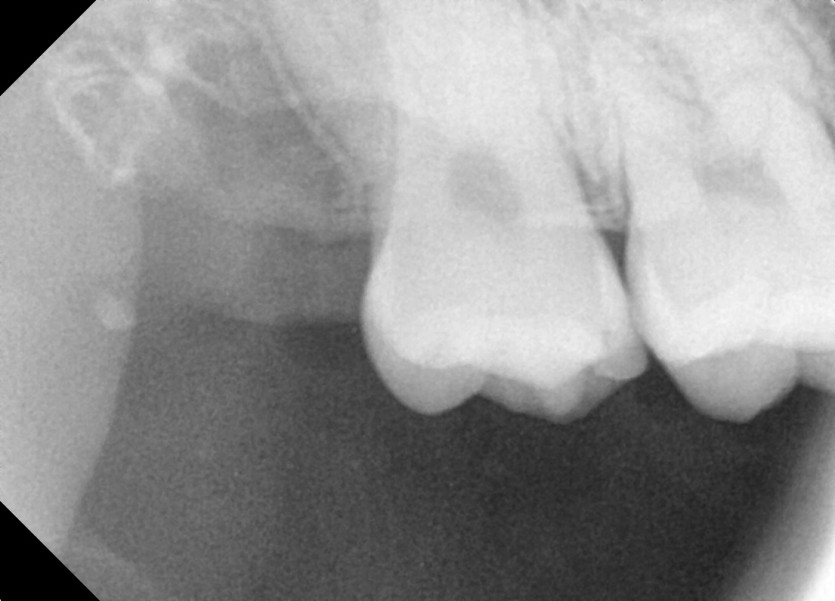

#18,28,38,48 사랑니 발치

구강 외과 전문의가 당일 발치했습니다.